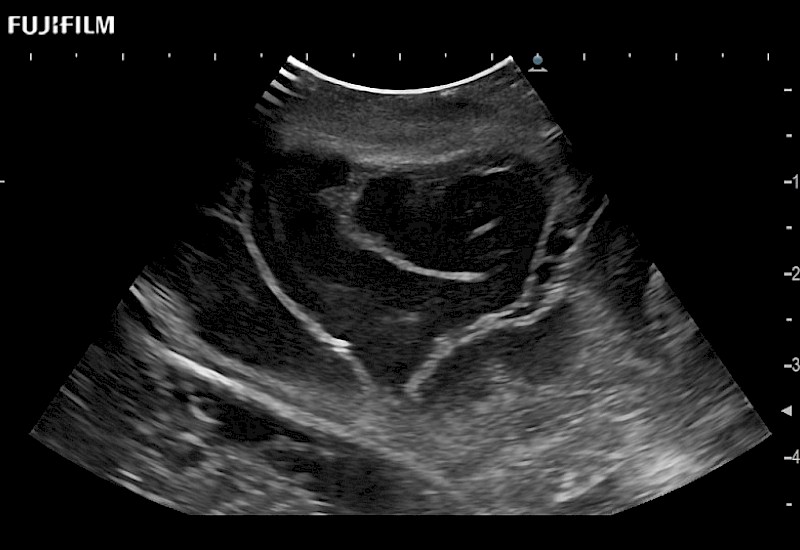

Extraordinary high-resolution digital imaging

Exceptional transducers

for use during: Cranial guidance, Burr-Hole guidance, Spinal Cord guidance, Pituitary guidance, Micro-Surgery guidance

Our dedication to neurosurgery allows us to offer superior image quality, outstanding system reliability and intuitive use of cutting edge technology.